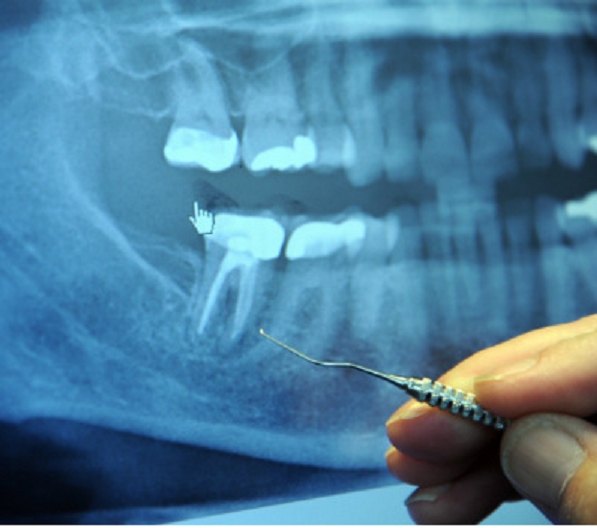

Root Canal Treatment... DONT DO IT.png

Root Canal Treatment... DONT DO IT.png (354.56 KiB) Viewed 23629 times